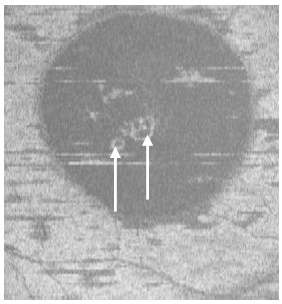

Case 3. A 37 year-old Hispanic male presented to clinic complaining of loss of vision for one month OS. He indicated that his surroundings “looked blurred, smaller and darker”. He reported having good health and taking no medications. The patient was a tobacco smoker. BVA were 20/20 OD and 20/60 OS. Preliminary tests including pupil responses were unremarkable OU. Blood pressure was 110/70 mm Hg. SLE was generally unremarkable with deep and quiet anterior chambers OU. Goldman tonometry measurements were 17 mm Hg OD and OS. DFE revealed healthy fundus and optic nerves OU with C/D ratios of 0.45/0.45. A CSD was observed encompassing approximately 3 DD at the macula OD (Figure 12). SDOCT confirmed the presence of a CSD and an isolated small PED. A small zone of hyper-reflectivity pattern in the subretinal space was observed proximal to the PED on the SDOCT. The outer retinal layer appeared to be indenting into the subretinal space slightly, proximal to the contact point of the uppermost tip of the hyper-reflective pattern. A hypo-reflective center and diffuse hyper-reflective edgings distinguished the hyper-reflective pattern. The POS appeared thick and somewhat granulated and the IS/OS junction line was not visible (Figure 13). Five concentric, hyper-reflective circles corresponding to upraised retinal layers, namely ILM/NFL,GCL, INL, OPL and ONL were visible on the “en-face” and 3-D imaging scans (Figure 14a-b). On 3-D imaging a slight “dipping” of the outer retinal layer into the subretinal space was also noticed (Figure 14b). The PED on the “en-face” scan appeared nearly round having a hypo-reflective center and hyper-reflective borders (Figure 15). Smoking cessation was recommended as part of the management. During the last follow-up visit (3 month from initial presentation) the patient indicated significant improvement but was not completely asymptomatic. He had reduced the amount of tobacco smoking. BVA were 20/20 OD and 20/25 OS. The CSD was still visible on fundus examination and the SDOCT confirmed the CSD to be partially resolving with a collapsed PED (Figure 16). The hyper-reflective pattern originally seen proximal to the PED was no longer visible. Granulation of the POS appeared to be more widespread but comparatively seemed to be thinner. The IS/OS junction line was now visible. A follow-up appointment was scheduled for one month but the patient did not return to clinic.

Figure 13. CSD observed on SDOCT with an isolated small PED (dark arrow) (case 3). A small subretinal hyper-reflective pattern is evident proximal to the PED (arrow head). The outer retinal layer appears slightly indented as it contacts the tip of the subretinal hyper-reflective pattern (arrow). A hypo- reflective center and diffuse hyper-reflective edgings distinguish the subretinal hyper-reflective pattern. The POS appears thick and somewhat granulated and the IS/OS junction line is not visible.

Figure 14a-b. Five concentric hyper-reflective circles (a) (ILM/NFL, GCL, INL, OPL and ONL) are visible on SDOCT “en-face” scan (case 3). The upraised layers and a PED (large white arrow) are observed on 3-D imaging (b). A slight “dipping” of the outer retina layer into the subretinal space is evident (small white arrow) (b).

Figure 15. The PED appears on “en-face” scan to be nearly round with a hypo-reflective center and hyper-reflective borders (arrow).

Figure 16. At 3 month from initial presentation, the CSD on SDOCT appears partially resolving with a collapsed PED at the last visit (case 3). A subretinal hyper-reflective pattern is no longer visible. The POS appears to be more granulated, widespread and comparatively thinner (arrows). The IS/OS junction line is visible.